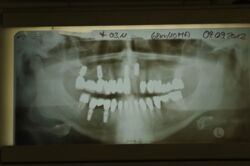

Der Patient hatte das Gefühl ein Implantat sei locker.

Knapp daneben. Ein langjährig wurzelgefüllt versorgter Kronenzahn gibt seinen Geist auf.

Die Krone ist gut, nur leider nicht mehr der gefüllte Wurzelstumpf darunter.

Es geht um Zahn 22.

Daneben steht ein wurzelgefüllter und erhaltungswürdiger Zahn 23

Daneben andererseits Implantat 11, das im Rahmen einer Brückenversorgung in den ersten Quadranten hinein reicht.